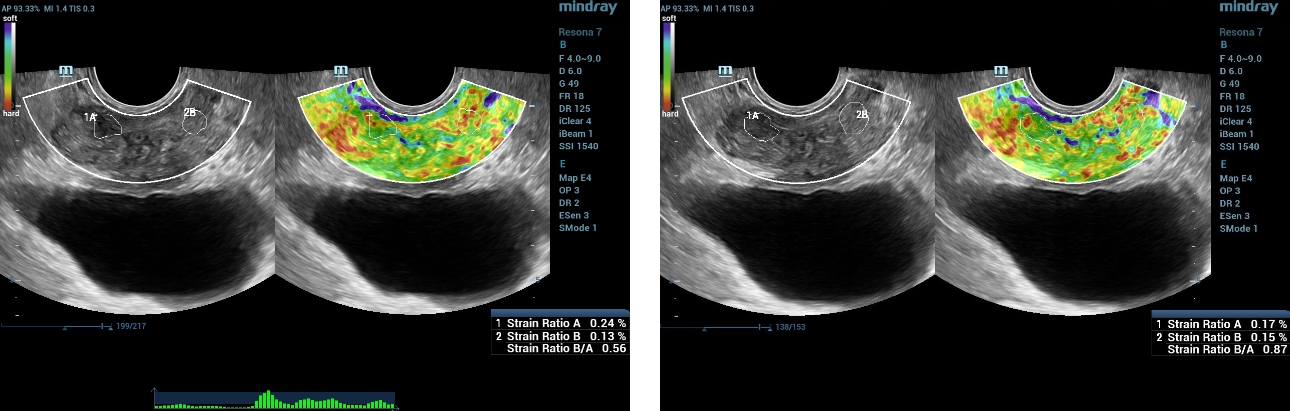

?????(Strain Elastography) ??

Resona7? Natural Touch Elastography? ???? ???? ??? ??????. ?? ??? ??? ??? 0.56-0.87 ??? ???? ?? ???? ?? ? ??? ??? ???? ?????.